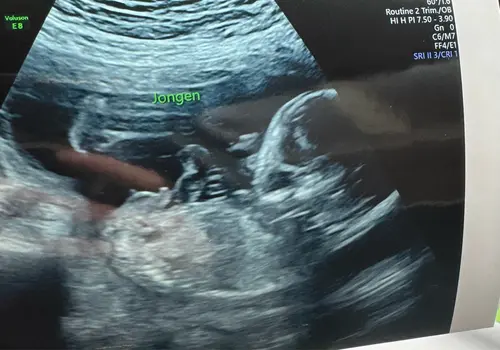

Toch even uit ‘respect’ naar een andere dame die echt specifiek geleerd heeft voor medisch en geslachts echo’s. Wel heen gegaan met het idee dat het gewoon een meisje zou zijn. Maarja zoals te zien op de foto een jongetje. Blijkt dat de eerste foto van ‘een meisje’ het balzakje bleek te zijn en ze eigenlijk iets hoger had gemoeten tijdens de echo. 🙈🩵

Met mijn 13 weken echo had ik gevraagd of ze kon zeggen wat het geslacht is vanwege 2 eerdere miskramen (wilde wat hebben om van die angst af te kunnen stappen) en ze zei een meisje, heel stellig. Met 15 weken geslachtsbepalingsecho gehad en weer stellig een meisje. Beide echoscopisten hebben heel veel ervaring. De eerste keer werd er alleen van onder gekeken. En die ander legde aan ons uit dat ze altijd van 2 kanten bekijkt: de zijkant (nub) en onderkant (potty). Dat liet ze nog een keer zien aan ons en het het is echt een meisje 🥰